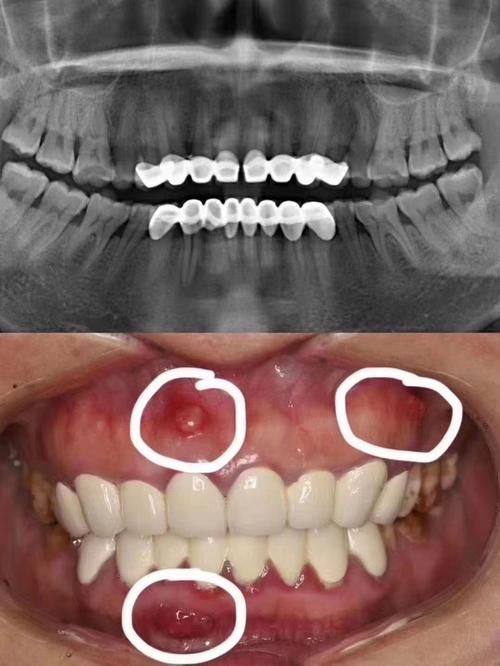

牙周炎诊疗:有效干预牙周炎、牙槽骨吸收、牙龈萎缩等疑难牙周问题

韩国江南人爱牙科牙周炎诊疗:1000元起